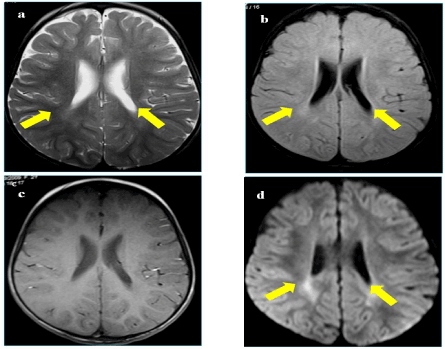

A one years old boy presented to Neuropediatric department with psychomotor delay. He is the second child of first degree consanguineous healthy parents. His sister died at the age of 18 months from a similar illness. He had a personal history of perinatal asphyxia, recurrent respiratory infections and hyperthermia. Examination showed irritability, axial hypotonia, spastic tetraparesis, dystonia, oculogyre crisis and increased sweating. Brain MRI showed frontal cortical atrophy and periventricular T2 hyperintensity (Figure 1).

Figure 1. a. Cerebrospinal MRI showing an hypersignal T2; b. FLAIR; c. prominent periventricular white matter posteriorly and appearing in isosignal T1; d. with restriction of ADC on the weighted diffusion sequence as b1000